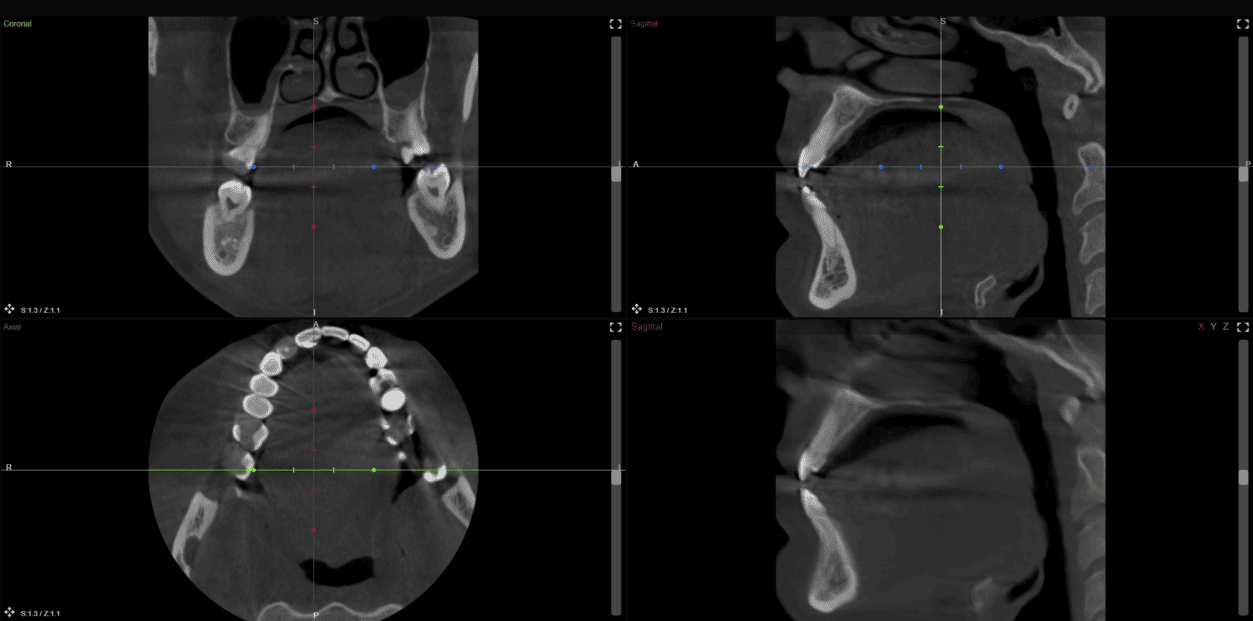

Any CT scans

Different devices